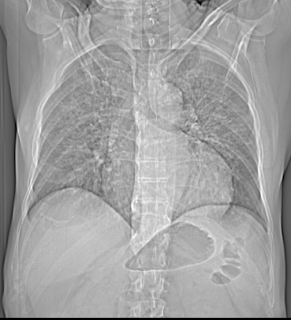

Clinical Profile : HIV positive status. There is presence of ground glass haziness with interstitial interlobular and intralobular septal thickening noted in both lungs with symmetrical and perihilar distribution, sparing the lung peripheries. No evidence any cystic lucencies are noted. Possibility of Pneumocystis Carnii. Case Submitted by Dr Swati Shah, MD, FRCR & Dr Sumer Sethi.

Features of P. Carnii on CT include:

- ground-glass pattern

- predominantly involving perihilar or mid zones

- there may be a mid, upper or lower zone predilection depending on whether the patient is on prophylactic aerosolised medication , if they are, then the poorly ventilated upper zones are prone to infection , whereas in those who are not the lower zones are more frequently involved

- reticular opacities or septal thickening may also be present

- a crazy paving pattern may therefore be seen when both ground-glass opacies and septal thickening are superimposed on one another

- pneumatocoeles

- pleural effusions are rare